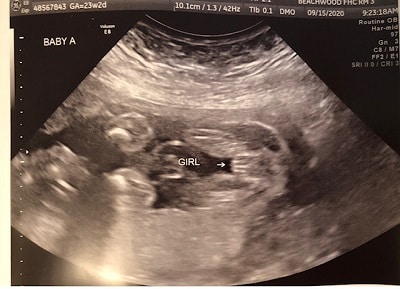

Ultrasound Photos at 23 Weeks Pregnant With Twins